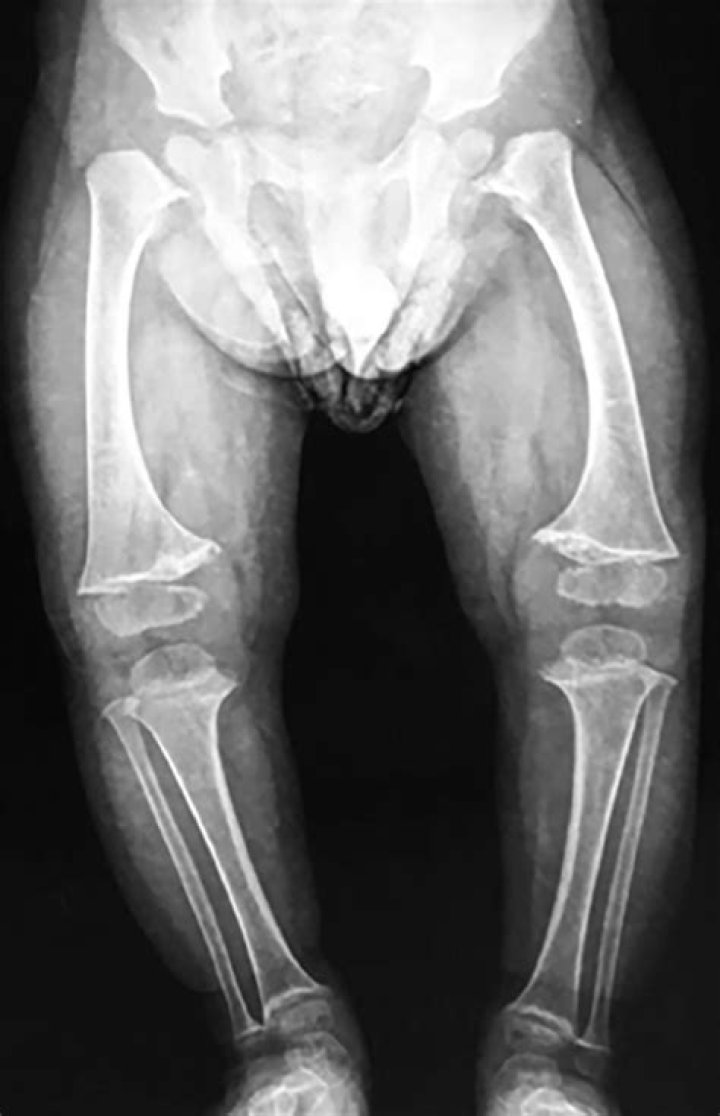

Metaphyseal chondrodysplasia, Schmid type (MCDS), is a very rare inherited disorder characterized by short stature with abnormally short arms and legs (sh...